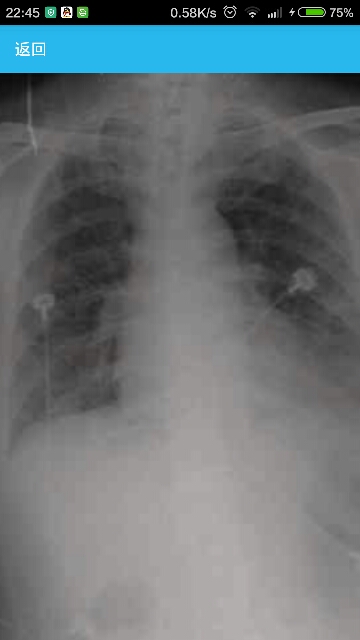

患者女性,61岁,因“发热伴喘憋7天”入院。 病史患者入院前7天,无明显诱因出现发热,最高体温可达39 ℃,伴喘憋和发冷感,无明显寒战,偶有咳嗽,但无明显咳痰,体温高时可感轻度头痛,无意识障碍,无胸痛,无尿频、尿急及尿痛,无腹痛及腹泻。入院前查血常规示,白细胞计数(WBC)13.10×109/L。胸部CT示,双肺内中带多发片状密度增高影。给予头孢噻肟钠和盐酸左氧氟沙星治疗。治疗6天后,患者仍间断发热,体温可达39 ℃。患者4个月前被诊为不典型膜性肾病,给予甲泼尼龙、免疫抑制剂环磷酰胺及抗凝治疗。类固醇性糖尿病2个月。 临床表现体温36.5 ℃,双肺呼吸音粗,未闻及明显干湿性音。双下肢轻度凹陷性水肿。余未见明显异常。 辅助检查WBC 6.6×109/L,中性粒细胞比例90.74%,血红蛋白82 g/L。血沉、C反应蛋白水平显著增高。血气分析:pH值7.53,动脉血二氧化碳分压34 mmHg,动脉血氧分压78 mmHg,动脉血氧饱和度97%。巨细胞病毒(CMV)抗原检测9.36×103 copies/ml;肺泡灌洗液巨细胞病毒DNA检测2.98×104 copies/ml;肺泡灌洗液细菌培养、抗酸杆菌检查、卡氏肺孢子菌检查阴性。影像学检查:胸部X线示,双肺见斑片状高密度影,右侧肋膈角模糊。胸部CT示,双肺见多发斑片、磨玻璃影,伴小叶间隔增厚和双侧少量胸腔积液。 诊断:巨细胞病毒肺炎 治疗给予更昔洛韦、丙种球蛋白及抗生素治疗,呼吸机辅助呼吸。复查X线示,双肺见斑片样密度增高影及索条影,双肋膈角锐利,患者好转。